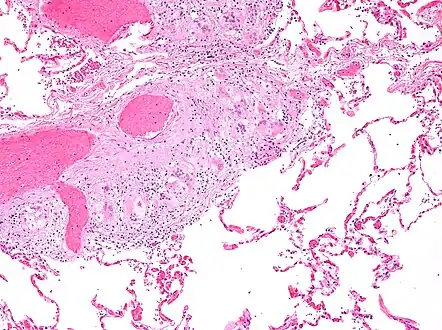

Micrograph of asteroid bodies in pulmonary sarcoidosis. H&E stain.